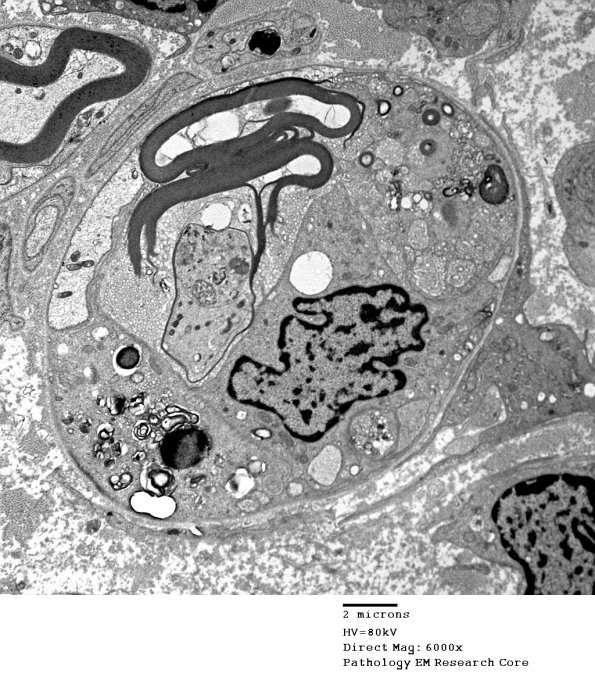

An axon is surrounded by macrophage processes containing myelin debris. A macrophage has applied its processes to the external surface of the axon at this level. (electron micrograph)